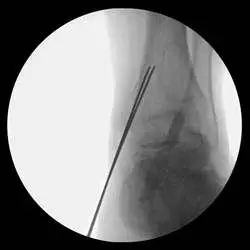

This is a pic of the implant getting mapped out for placement in the distal tibia

This is the guide for the tibia component of the implant